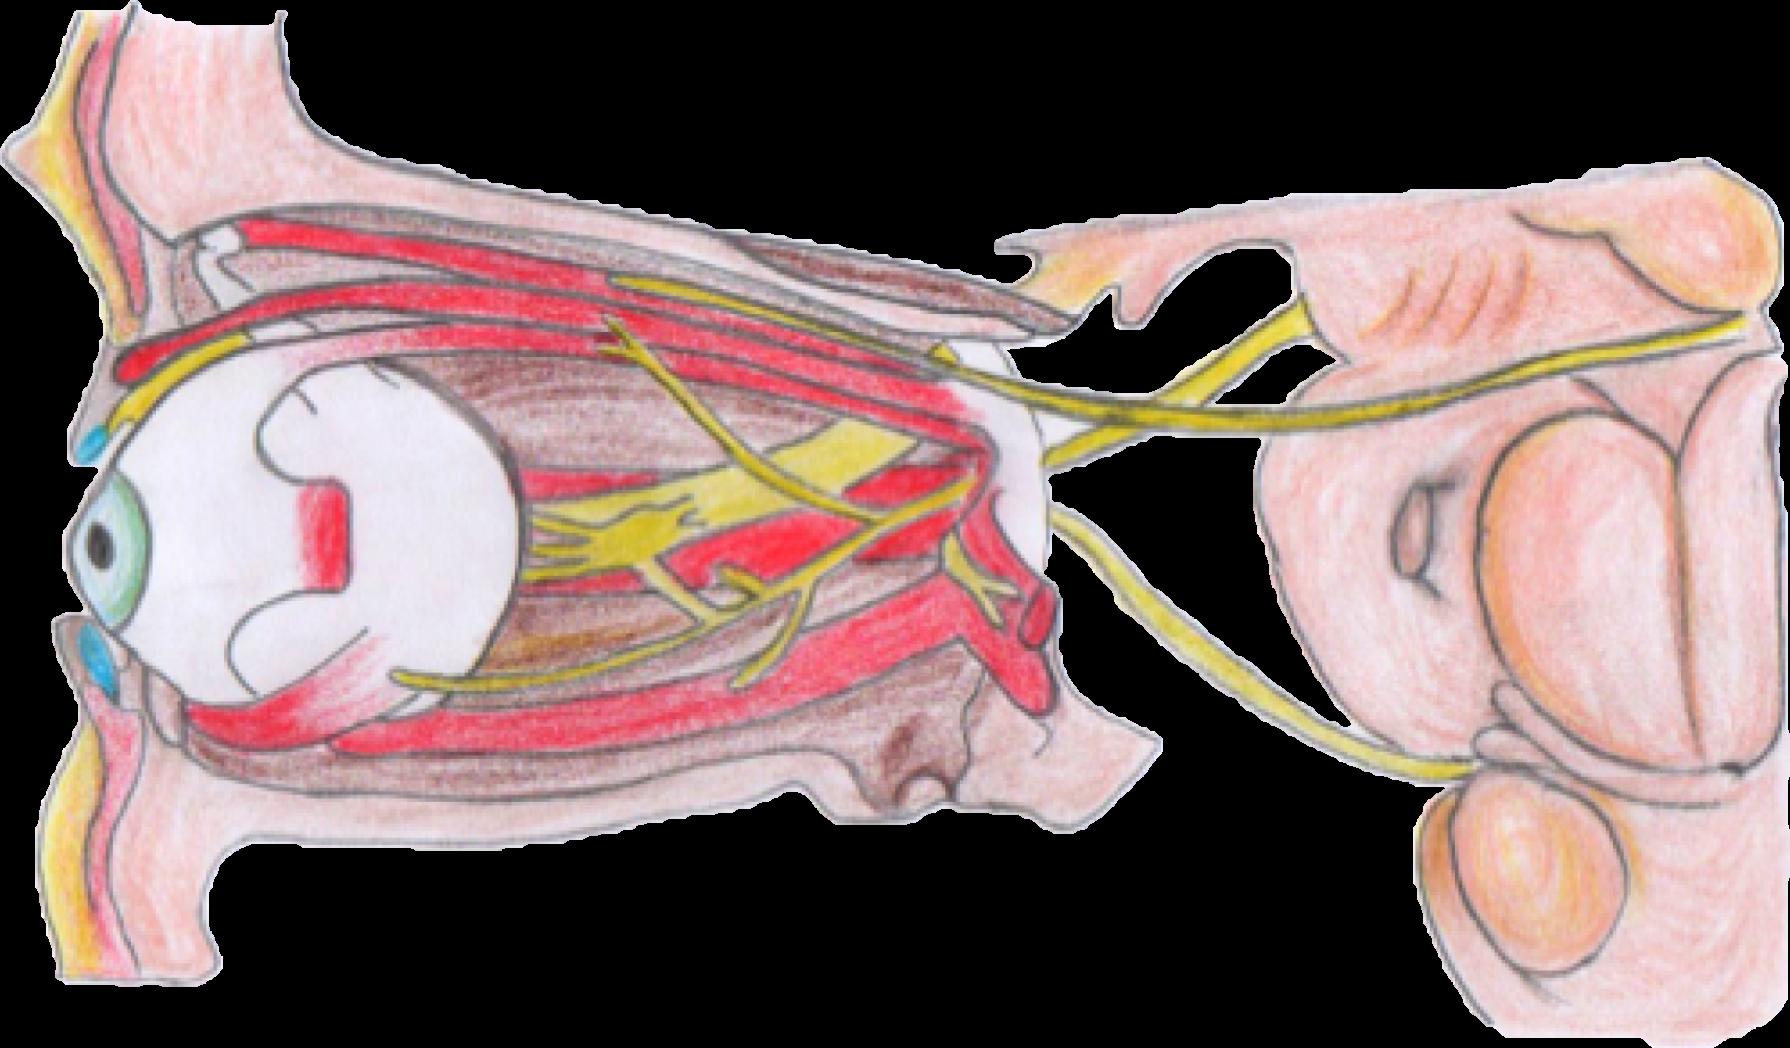

ORGANIZACION DE SISTEMA NERVIOSO PERIFERICO (PARES CRANEALES) Tema 3 Semana 6 NERVIO OLFATORIO Bulbo olfatorio Nervio nasopalatino Nervio nasociliar Lamina cribosa NERVIO OLFATORIO (I PAR) Características Las celulas olfatorias reaccionan ante los agentes quimicos ambientales. Globo ocular Cintilla óptica Papila Radicaciones ópticas NERVIO ÓPTICO Córtex visual Núcleo geniculado Quiasma óptico NERVIO ÓPTICO (II PAR)

NERVIO OCULOMOTOR (III PAR)

Características

Se encarga del movimiento de los ojos, elevacion del parpado, contraccion pupilar.

Musculo oblicuo superior

Musculo recto superior Musculo elevado al parpado superior

Nervio troclear

Rama superior del nervio oculomotor

NERVIO OCULOMOTOR

Arteria carótida interna

Iris

Nervio trigémino

Musculo oblicuo inferior

Musculo recto inferior

Ganglio ciliar

Rama inferior del nervio oculomotor

NERVIO TROCLEAR (IV PAR)

Musculo obliquo superior

Arteria cerebral posterior

Nervio troclear (IV)

Características

Su funcion es el movimiento de los ojos arriba y abajo.

Arteria cerebral superior

Nervio oculomotor (III)

NERVIO TRIGÉMINO Rama oftálmica Rama maxilar Rama mandibular NERVIO ADBUCENTE Nervio vestibulococlear Nervio facial Nervio trigémino Nervio troclear Nervio oculomotor Quiasma óptico Musculo recto superior Musculo oblicuo superior Tróclea Musculo elevador del parpado superior Musculo oblicuo inferior Musculo recto inferior Ganglio ciliar Musculo recto medial Musculorectolateral NERVIO ABDUCENTE (VI PAR) NERVIO TRIGEMINO (V PAR)

Controla principalmente la musculatura de la masticacion y la sensibilidad facial.

lEs el responsable del giro del ojo hacia afuera.

Características

Características